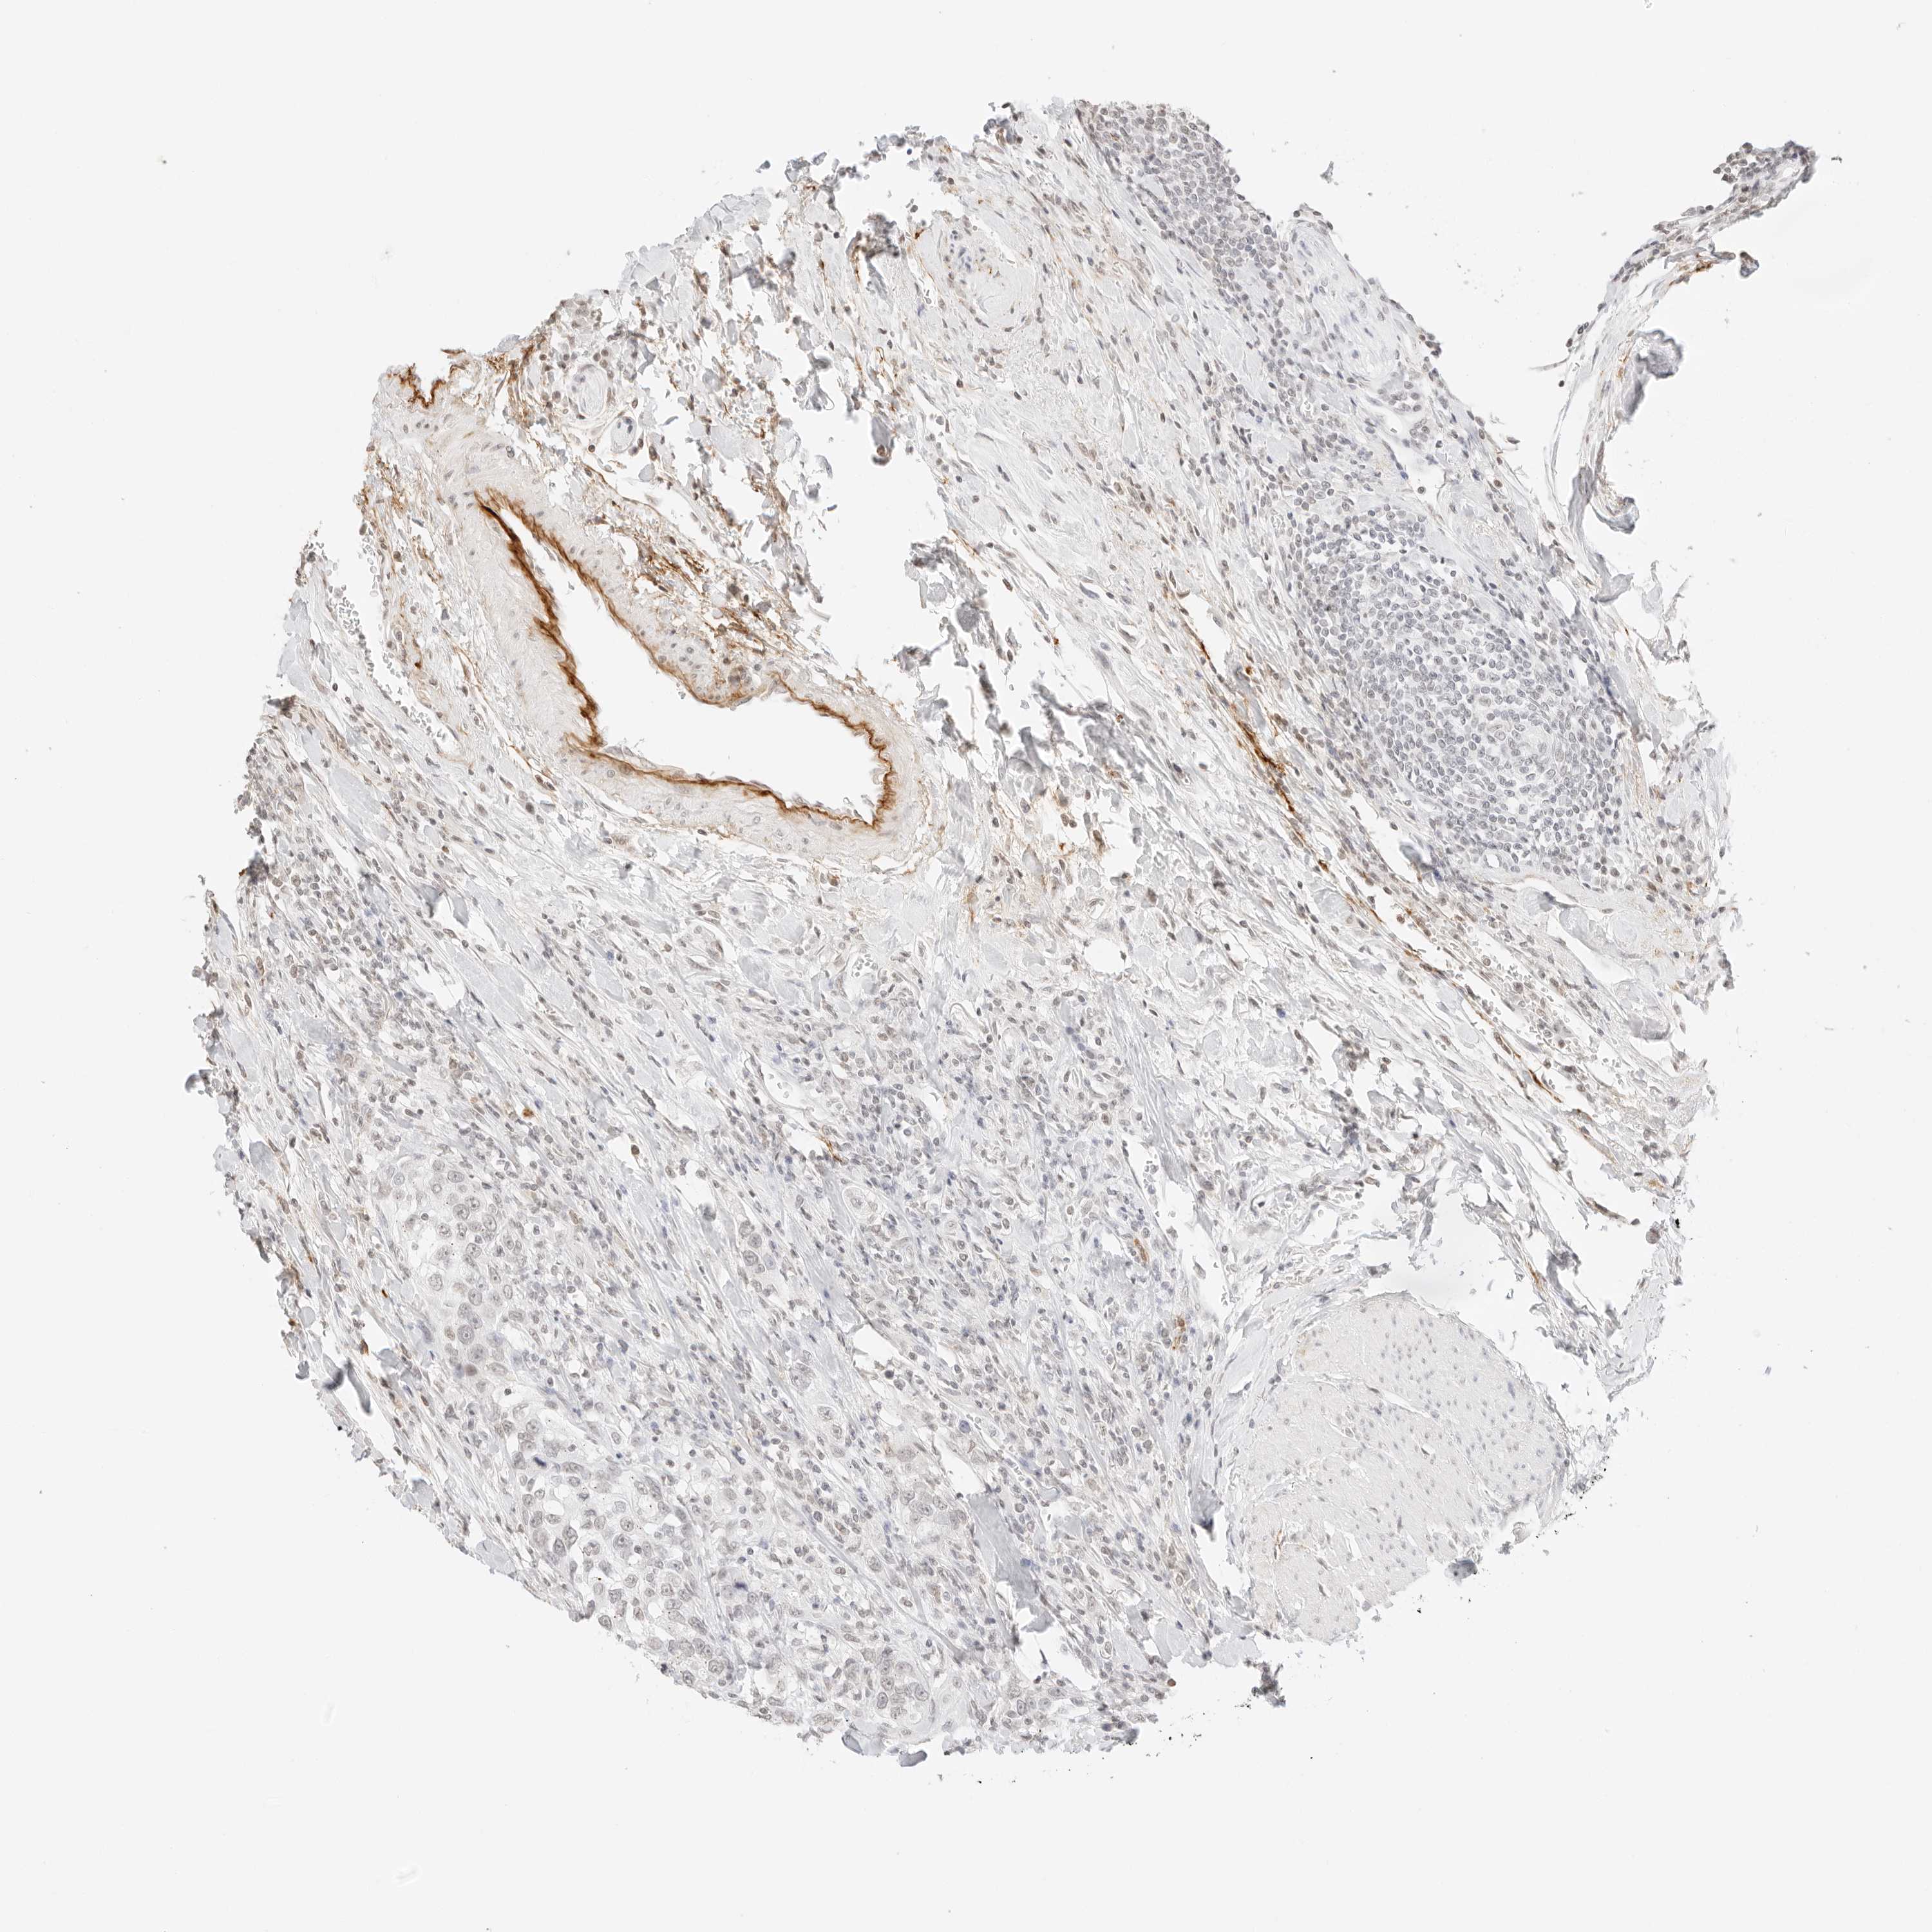

UROTHELIAL CANCER - Protein expressioni

A mouse-over function shows sample information and annotation data. Click on an image to view it in a full screen mode. Samples can be filtered based on level of antibody staining by selecting one or several of the following categories: high, medium, low and not detected. The assay and annotation is described here.

Note that samples used for immunohistochemistry by the Human Protein Atlas do not correspond to samples in the TCGA dataset.

Antibody stainingi

Antibody staining in the annotated cell types in the current human tissue is reported as not detected, low, medium, or high, based on conventional immunohistochemistry profiling in selected tissues. This score is based on the combination of the staining intensity and fraction of stained cells.

Each image is clickable and will lead to virtual microscopy that enables deeper exploration of all samples and also displays staining intensity scores, fraction scores and subcellular localization as well as patient and tissue information for each sample.

Antibody HPA000848

Antibody HPA000868

Antibody CAB025843

Staining

High

Medium

Low

Not detected

Intensity

Strong

Moderate

Weak

Negative

Quantity

>75%

75%-25%

<25%

None

Location

Nuclear

Cytoplasmic/membranous

Cytoplasmic/membranous,nuclear

Urothelial carcinoma, High grade

Urothelial carcinoma, Low grade